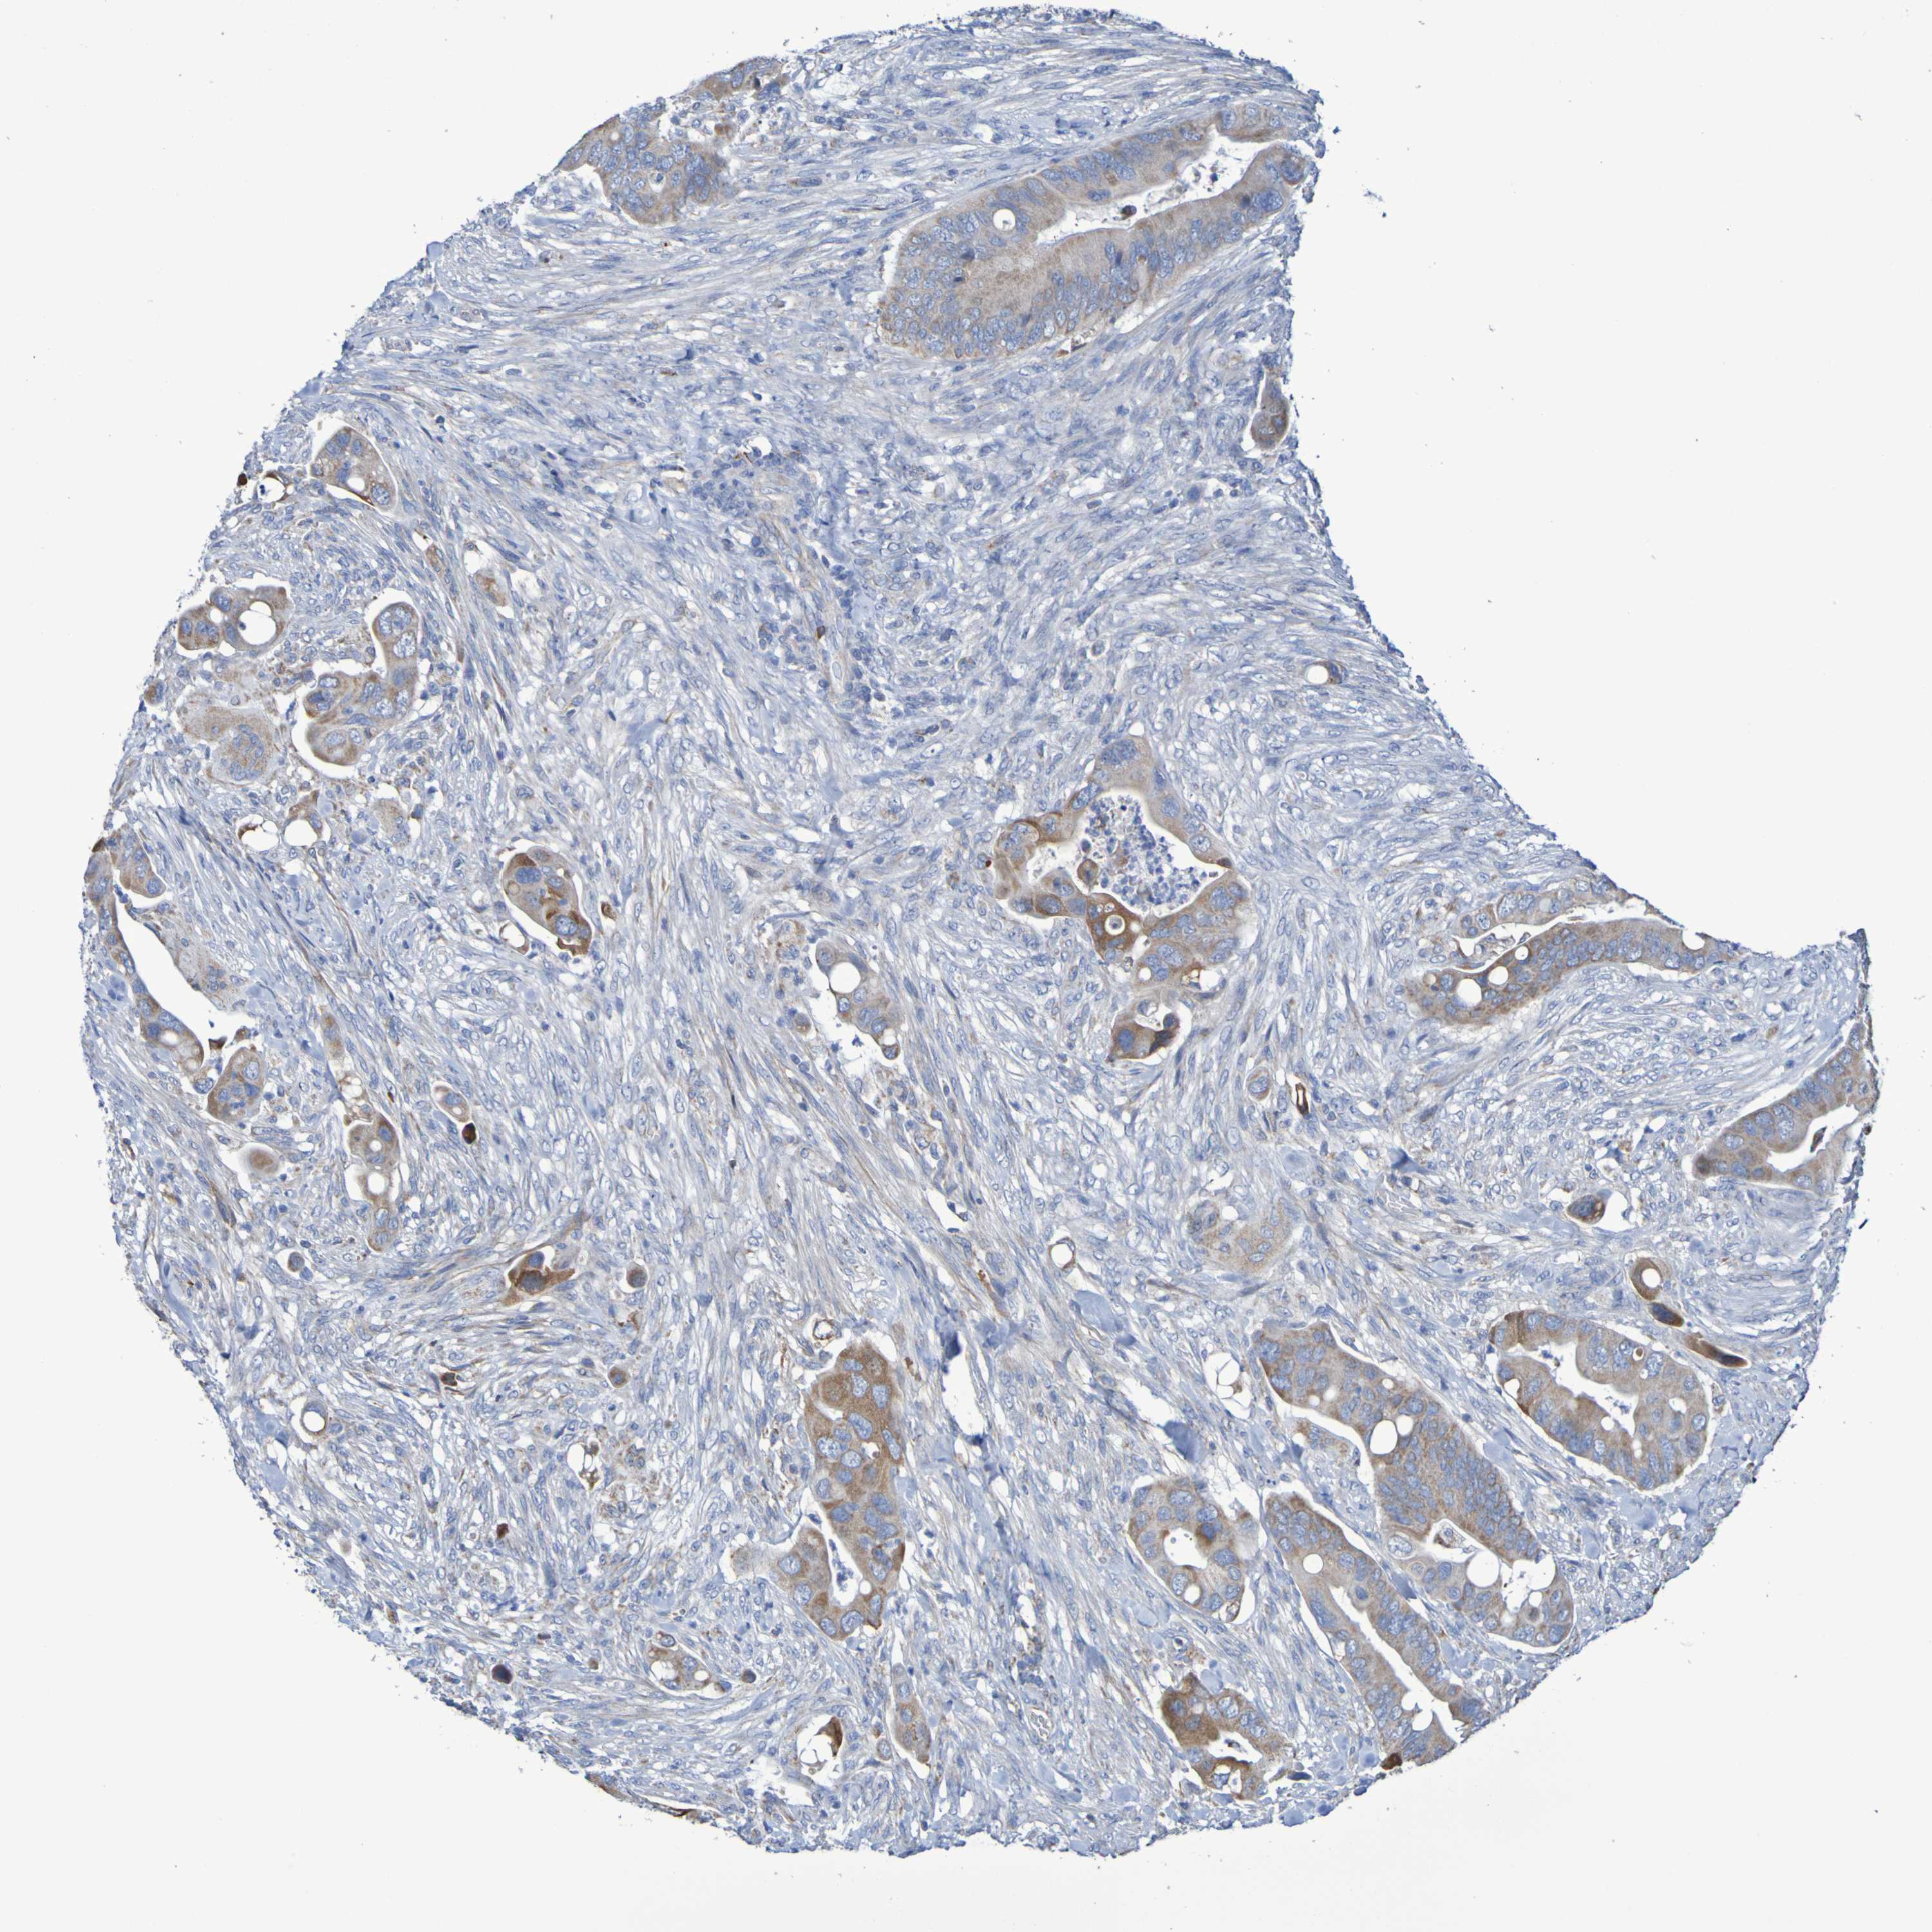

CANCER COLORECTAL CANCER Show tissue menu

Colorectal cancer

Human cancer

Colon adenocarcinoma